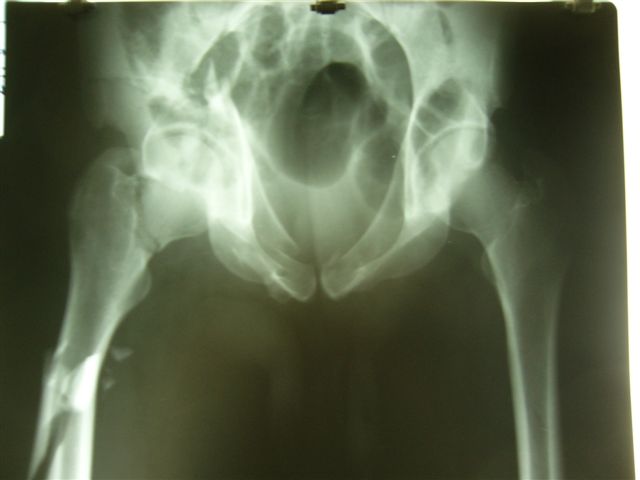

Anatoly F Lazarev 03 Сентябрь 2004, 22:18

Женя! Класный перелом. Отлично репонируется изнутри таза, но лучше фиксированть сзади. Классический перелом для двустороннего доступа.

Однако есть альтернатива. Репозиция из подвздошного доступа тазовыми щипцами с разнодлинными браншами или тазовым пистолетом, а фиксация задней колонны через седалищный бугор или тазрвыми винтами 4,5 или каннюлированными 6,5 или 7,3. По-моему я посылал на ортофорум такой снимок, когда жаловался на ишемический неврит седалищного нерва через сутки после операции. Не забудь про шейку бедра - мне кажется будет хорош длинный PFN любой фирмы, какую ты найдешь, а нет так UFN + miss a nail, как это здорово делают мои земляки - Ебурбуки. Пока.

Высылаю пример еще одного случая, остеосинтез пластиной из подвздошного доступа.